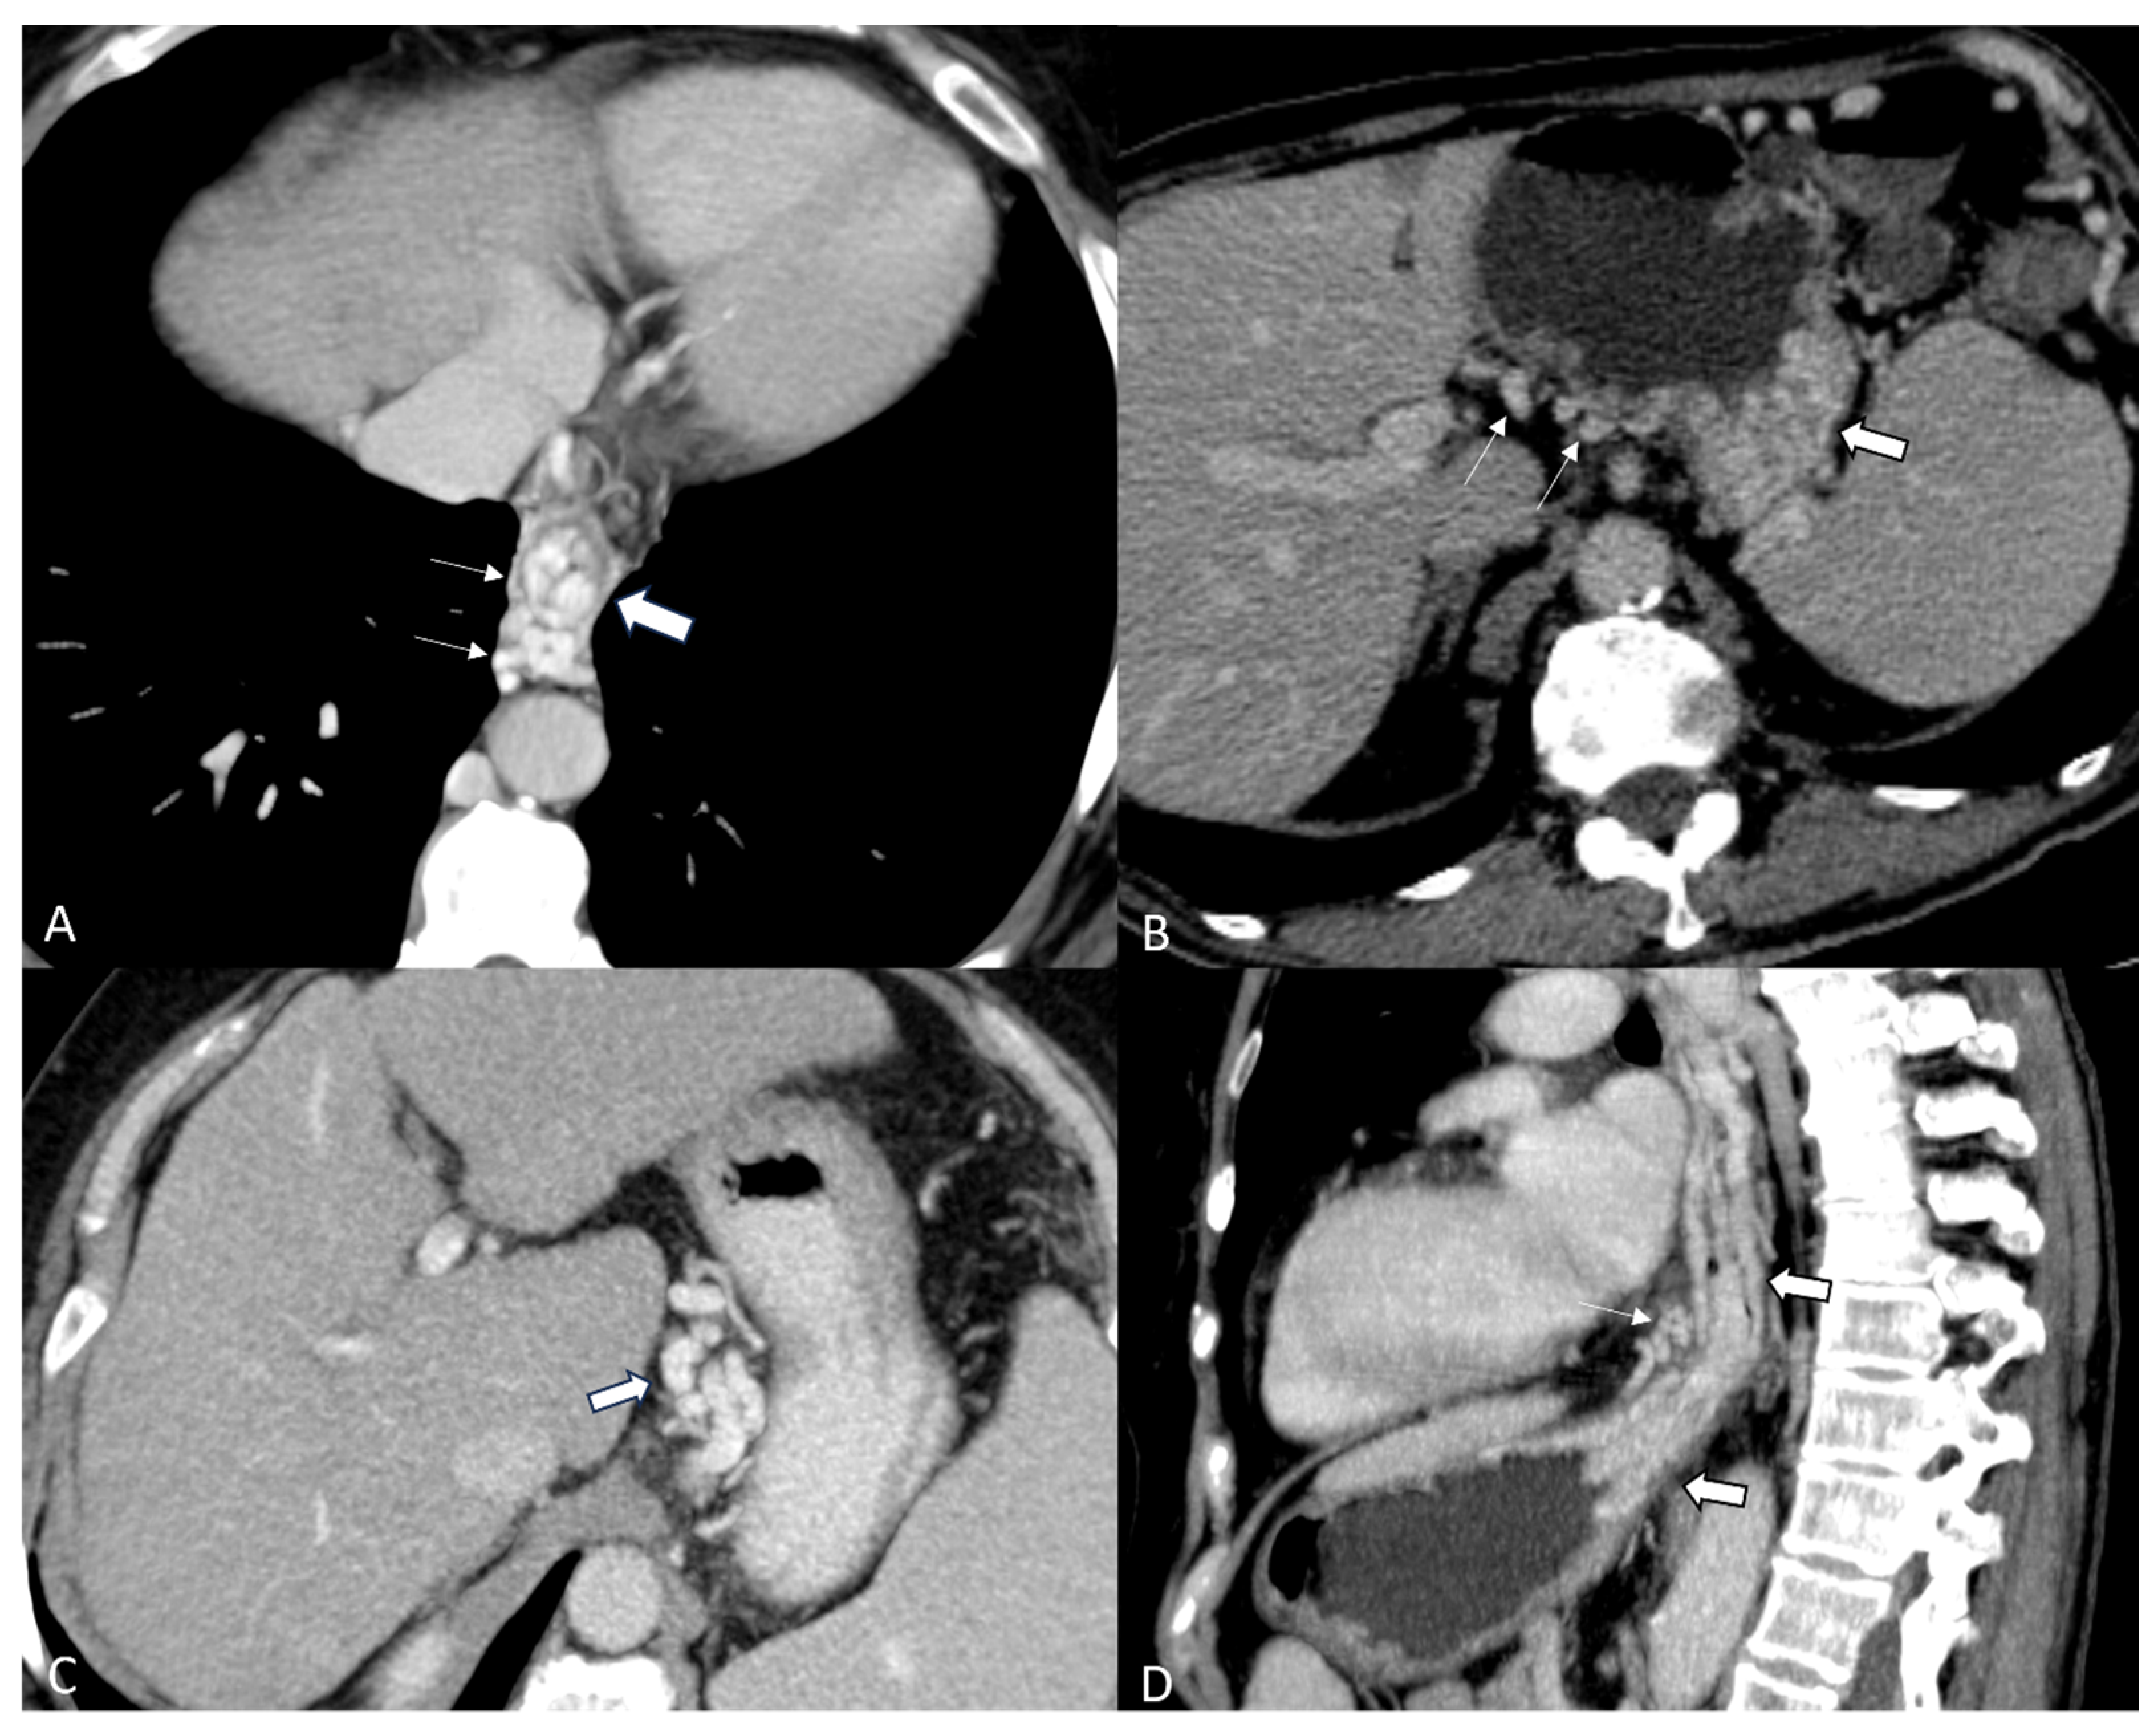

- Henseler, K.P.; Pozniak, M.A.; Lee, F.T.; Winter, T.C. Three-dimensional CT angiography of spontaneous portosystemic shunts. Radiographics 2001, 21, 691–704. [Google Scholar] [CrossRef]

- Yi, F.; Guo, X.; Zeng, Q.L.; Yang, B.; He, Y.; Yuan, S.; Arora, A.; Qi, X. Computed Tomography Images of Spontaneous Portosystemic Shunt in Liver Cirrhosis. Can. J. Gastroenterol. Hepatol. 2022, 2022, 3231144. [Google Scholar] [CrossRef] [PubMed]